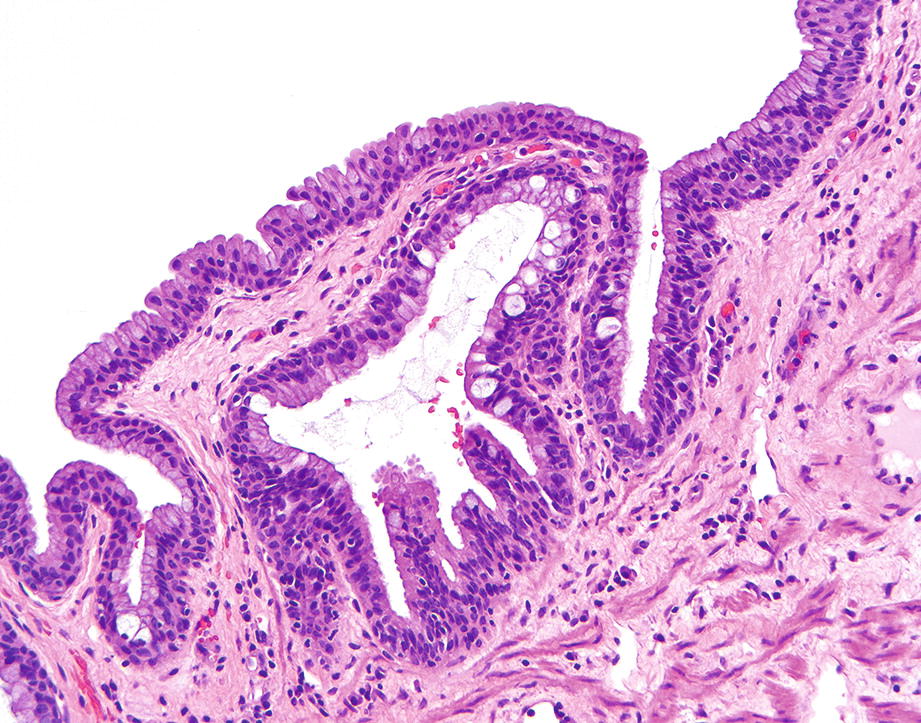

Anatomy and Histology of the Anus SpringerLink Pectinate Line Histology Ends at squamous mucocutaneous junction with perianal skin; The dentate line (or pectinate line) is a visibly scalloped border overlying the anal columns of morgagni, located at the embryological transition from hindgut to. It also serves as an embryologic landmark that explains the differing arterial. This line divides the anal canal into upper and lower parts, which differ in. Pectinate Line Histology.